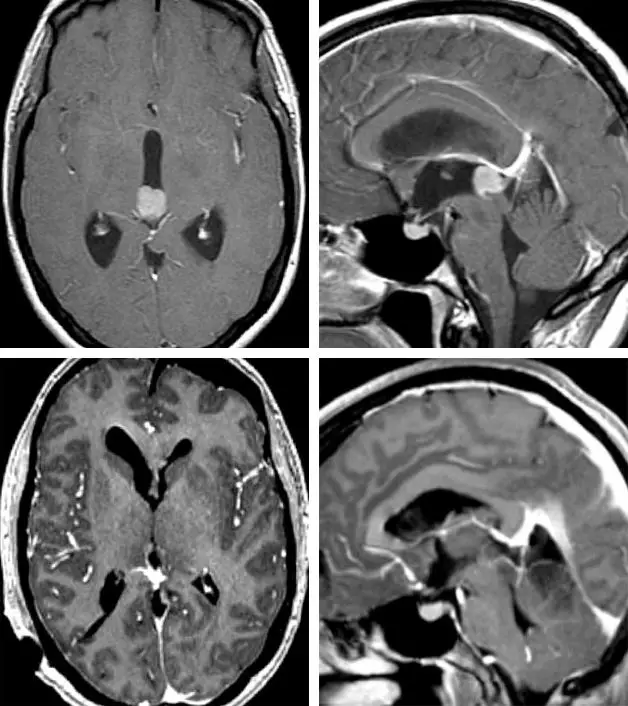

图2. 图为三脑室后部一中等分化松果体实质肿瘤(上排图)通过小脑上经脑室入路已切除该肿瘤(下排图)。(请参看图8)

图8. 患者取坐位,通过后正中小脑上入路显露图2显示的肿瘤。注意左侧顶盖的颜色差异(左图,吸引器顶端)。切除侵及顶盖部分后才可进入脑室并全切除肿瘤(右图)。